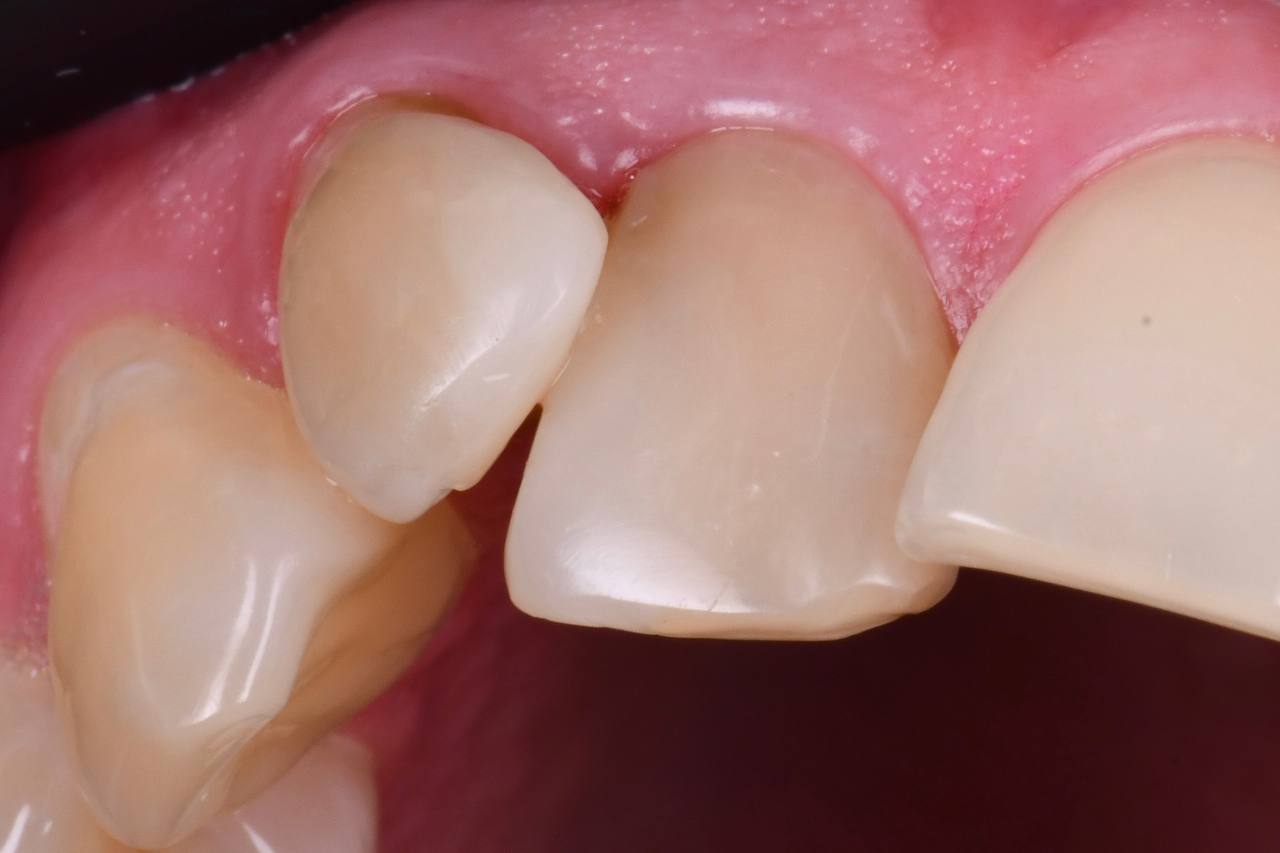

В детстве я упал и сломал передний зуб. Тогда мне сделали пломбу. Уже после ортодонтического лечения была проведена реставрация этого зуба. Теперь я очень доволен результатом работы! Спасибо!